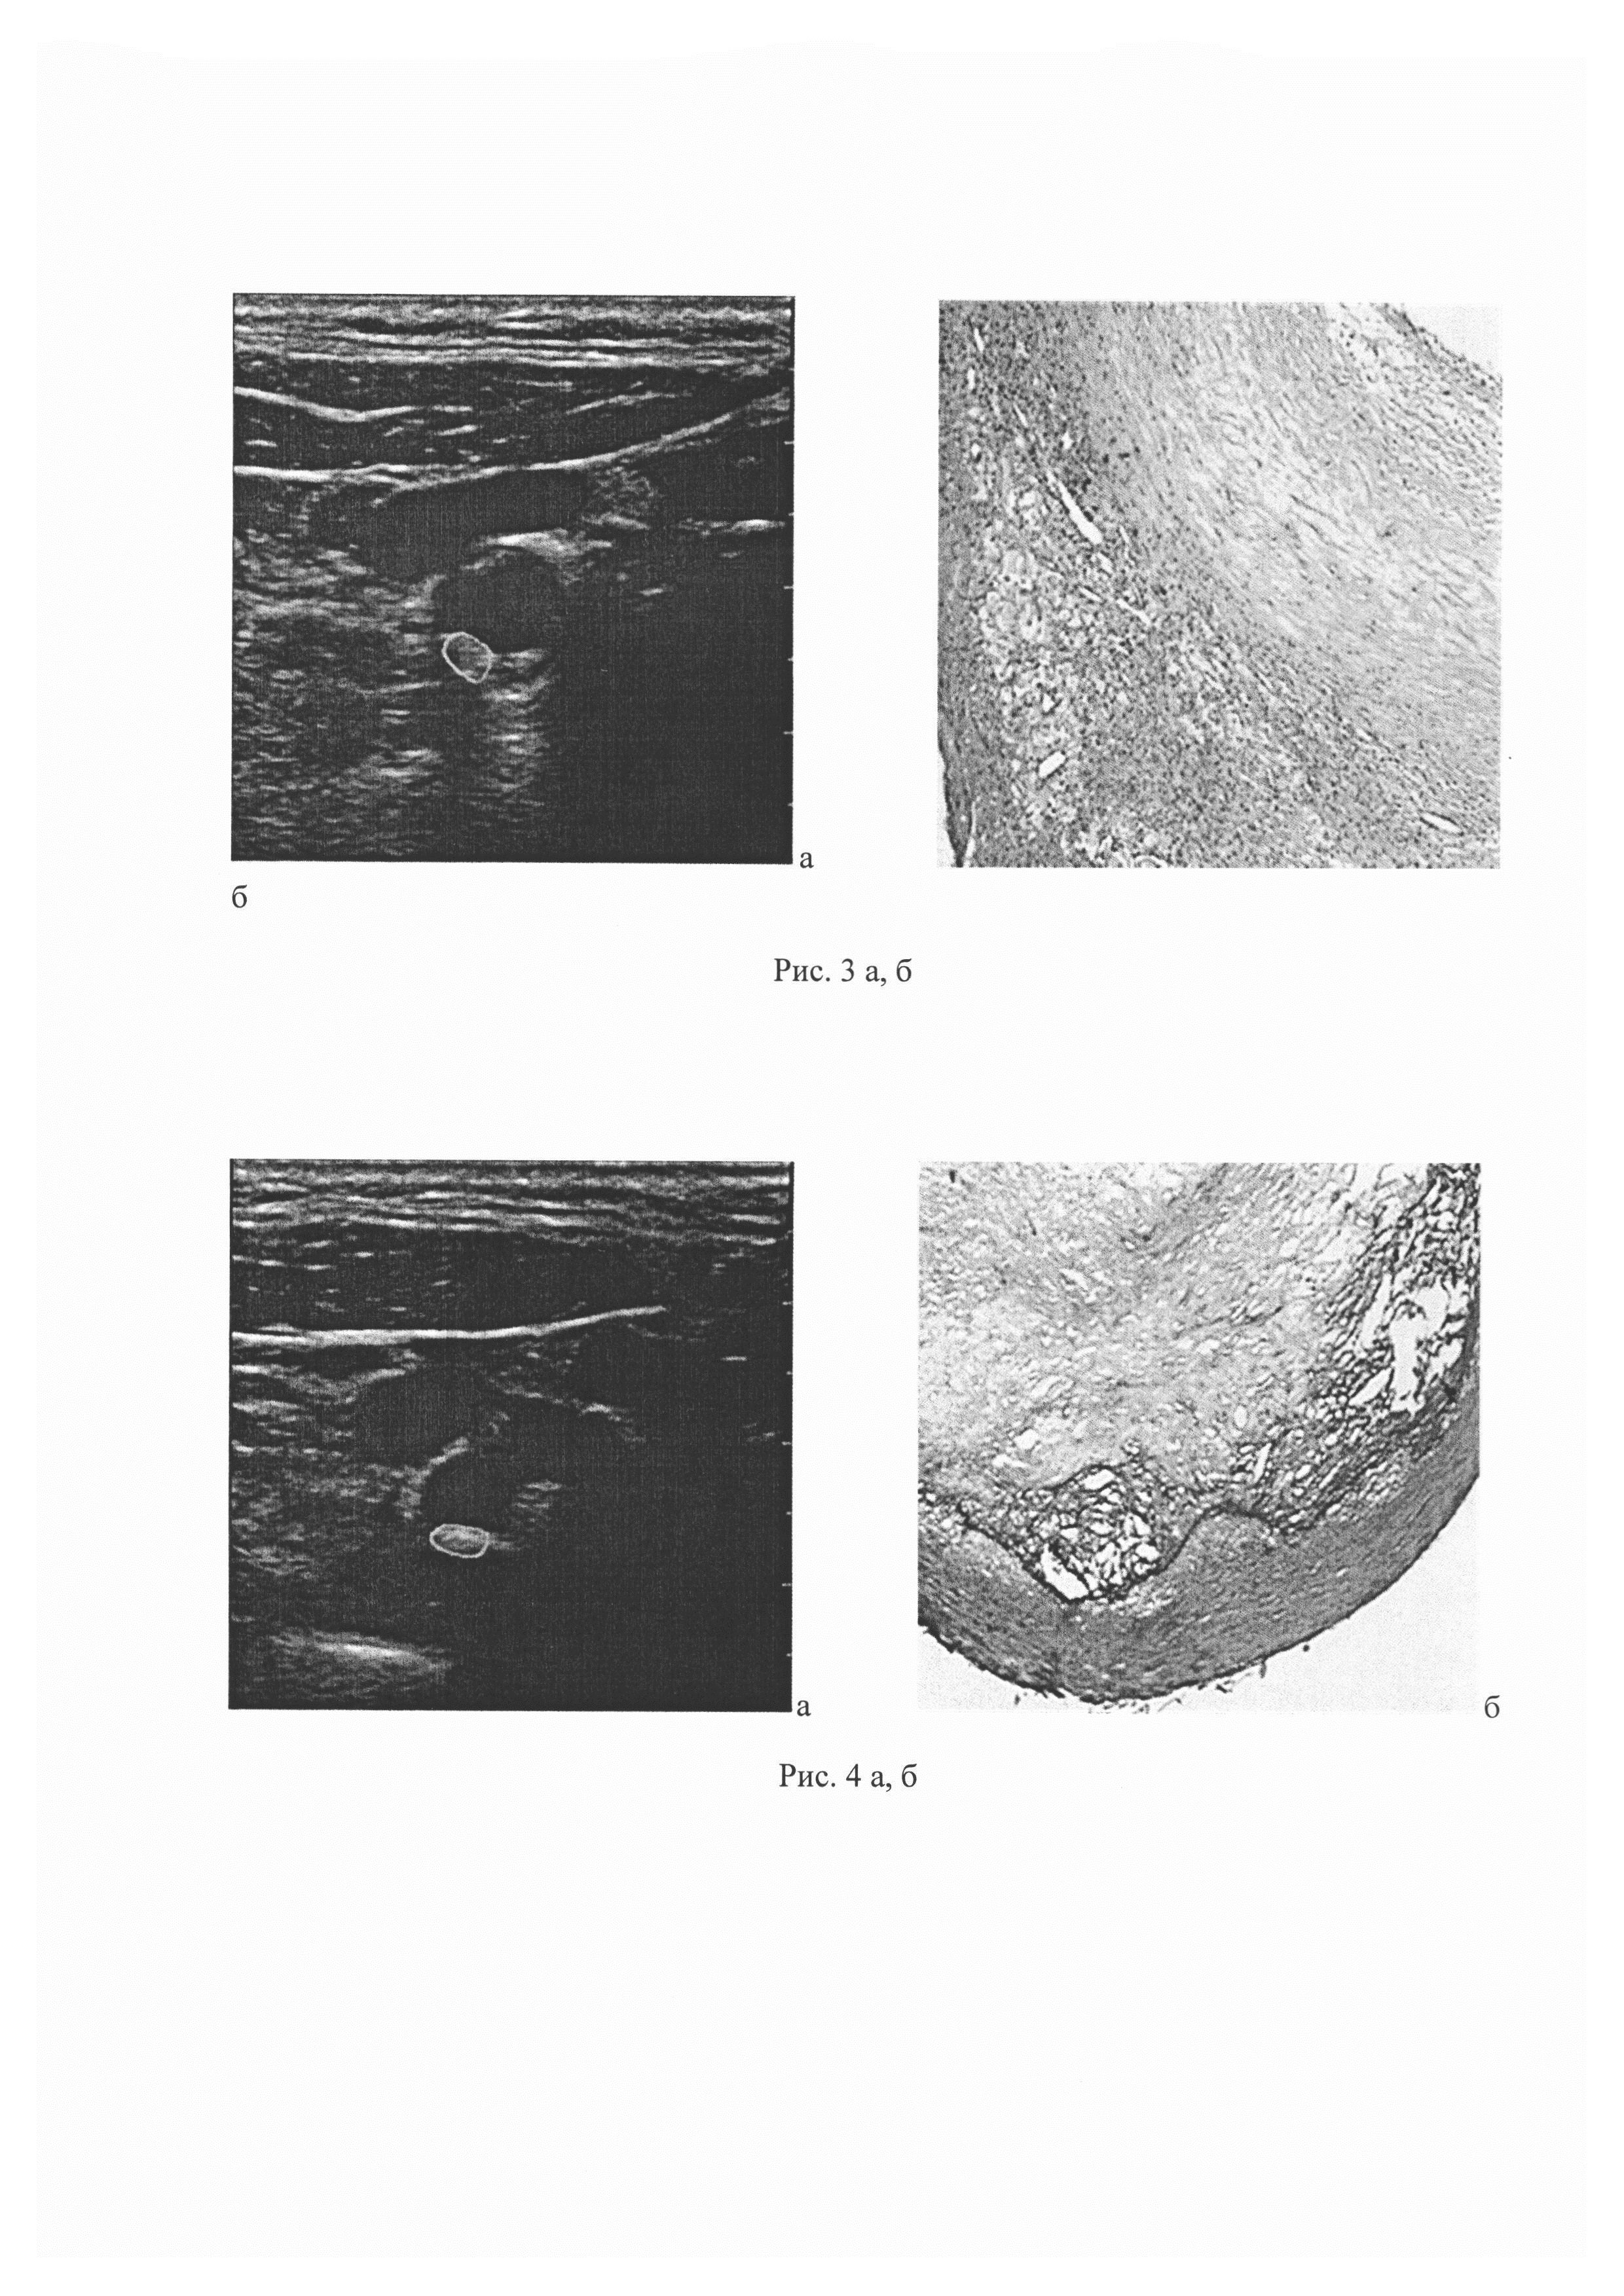

Изобретение относится к области медицины, в частности к неврологии и может быть использовано для определения структуры и морфологических особенностей атеросклеротической бляшки (АСБ). В развитии нарушений мозгового кровообращения (НМК) в каротидной системе мозга важна не только степень стеноза каротидного синуса (КС), но и структура АСБ: наличие прогрессирующего атероматоза на фоне воспалительного процесса, истончение и разрушение покрышки бляшки, инфильтрация бляшки макрофагами и другими клетками, деструктивные изменения вновь образованных сосудов с развитием кровоизлияний в бляшку. Эти процессы в АСБ повышают риск увеличения стеноза КС и его тромбоза, а также эмболии дистальных отделов внутренней сонной артерии (ВСА) и ее ветвей, что в конечном счете приводит к тяжелому НМК с развитием инфаркта мозга. Одним из наиболее эффективных методов предотвращения НМК в системе ВСА является каротидная эндартерэктомия (КЭЭ) - операция удаления АСБ из КС. Для оценки риска возникновения НМК и решения вопроса о показаниях к КЭЭ широко используется ультразвуковое исследование сонных артерий, позволяющее определить степень стеноза КС, а также эхоструктуру АСБ, отражающую их морфологический состав. В последние годы обсуждается необходимость (независимо от степени стеноза КС) проведения КЭЭ при наличии ультразвуковых признаков «нестабильной» структуры бляшки как у больных с перенесенным НМК, так и у пациентов с асимптомным стенозом (Madieke I.L., Fiona K., Bonati L.H., et al. Investigations of Carotid Stenosis to Identify Vulnerable Atherosclerotic Plaque and Determine Individual Stroke Risk. Circulation. 2017; 81: 1246-53). С внедрением технологии количественного анализа компьютерных изображений появились новые возможности и для изучения структуры АСБ [Tegos T.J., Sohail М., Sabetai М.М., et al. Echomorphologic and histopathologic characteristics of unstable carotid plaques. Am. J. Neuroradiol. 2000; 21: 1937-44]. Разработана и методика сопоставления структуры и морфологических особенностей АСБ. Такие исследования, несмотря на их важность, все еще немногочисленны. Известен количественный метод определения однородности структуры атеросклеротической бляшки с помощью медианы серой шкалы или GSM (grey scale median). Изображения атеросклеротических бляшек, полученных с помощью стандартного УЗ-исследования в серой шкале, подвергались последующей компьютерной обработке. Осуществлялось количественное определение интенсивности (или эхогенности) атеросклеротической бляшки. При этом на изображении выбирались референсные зоны, такие как просвет сосуда (которому соответствует значение GSM 0-5) и его адвентициальный слой (GSM 185-195). Затем проводилось нормирование изображения и оценивалась эхогенность бляшки. По соотношению участков с низкой (GSM<50) или высокой (GSM>50) эхогенностью определяли однородность АСБ (М.М. Sabetai, T.J. Tegos, A.N. Nicolaides, S. Dhanjil, G.J. Pare and J.M. StevensReproducibility of Computer-Quantified Carotid Plaque Echogenicity: Can We Overcome the Subjectivity? Stroke. 2000; 31:2189-2196). Недостатками способа является его использование только для выяснения однородности АСБ. Известен способ определения структурных характеристик атеросклеротической бляшки сонных артерий посредством ультразвукового исследования в В-режиме, режиме тканевой гармоники и режиме недопплеровской визуализации кровотока и сравнения этих данных с данными гистологического исследования (Тимина И.Е., Бурцева Е.А., Скуба Н.Д. и др. Сопоставление структуры атеросклеротической бляшки в сонной артерии по данным комплексного ультразвукового и гистологического исследований. Ультразвуковая и функциональная диагностика, 2004, №3, с. 81-87). Однако способ не обладает достаточной точностью в отношении структурных характеристик атеросклеротической бляшки сонных артерий из-за отсутствия стандартизации протокола измерений. Данный источник информации рассмотрен в качестве ближайшего аналога. Технический результат заключается в повышении точности определения структурных характеристик атеросклеротической бляшки сонных артерий, за счет стандартизации протокола измерений позволяющего минимизировать их погрешность. Технический результат достигается тем, что определение структурных характеристик атеросклеротической бляшки сонных артерий проводят путем ее ультразвукового исследования, при этом ультразвуковое исследование атеросклеротической бляшки проводят на глубине 5,0-10,0 мм в области наибольшего сужения просвета сонной артерии в продольной и поперечной проекциях в В-режиме с использованием линейного датчика с частотой излучения 11 МГц, со средней частотой кадров и максимальным динамическим диапазоном 60 дБ, затем на полученных неподвижных кадрах выделяют участки атеросклеротических бляшек размером до 1 см, и посредством программного обеспечения ультразвуковой системы, вычисляют медиану интенсивности ультразвукового сигнала в децибелах (дБ), отраженного от исследуемых участков атеросклеротической бляшки и при значении интенсивности ультразвукового сигнала 1,1-8,0 дБ определяют в атеросклеротической бляшке очаги атероматоза, 9,0-22,0 - очаги атероматоза с многочисленными кристаллами холестерина, 23,0-31,0 - очаги фиброза с диффузно расположенными липофагами и/или сосудами, 32,0-39,0 - очаги фиброза с кальцификатами, 40,0-45,0 - очаги кальциноза. Способ осуществляется следующим образом. Ультразвуковое исследование атеросклеротической бляшки выполняют на приборе Phillips iE33 на глубине 5,0-10,0 мм в продольной и поперечной проекциях. Исследование выполняют в серошкальном режиме (В-режим) с использованием линейного датчика с частотой излучения 11 МГц, со средней частотой кадров и максимальным динамическим диапазоном (60 дБ). Перед проведением каждого исследования устанавливают стандартные настройки ультразвуковой системы (настройки дисплея, цветовые эффекты, мощность, частота излучения). На неподвижных кадрах выделяют (обрисовывают) наиболее информативные, с точки зрения эхогенных характеристик, участки бляшек, размером до 1 см, расположенные в области наибольшего сужения просвета артерии. Далее с помощью программного обеспечения ультразвуковой системы вычисляют медиану интенсивности (в децибелах, дБ) ультразвукового сигнала, отраженного от исследуемых участков АСБ. Все изображения участков АСБ в В-режиме преобразовывают в формат JPG. При значении интенсивности ультразвукового сигнала 1,1-8,0 дБ определяют в атеросклеротической бляшке очаги атероматоза, 9,0-22,0 - очаги атероматоза с многочисленными кристаллами холестерина, 23,0-31,0 - очаги фиброза с диффузно расположенными липофагами и/или сосудами, 32,0-39,0 - очаги фиброза с кальцификатами, 40,0-45,0 - очаги кальциноза. В данное проспективное поисковое исследование были включены 90 пациентов (71 мужчина и 19 женщин, медиана возраста 62 (47-79) года), наблюдавшихся в отделении общей ангионеврологии Научного центра неврологии (Москва) за период с апреля 2015 г. по март 2016 г. У всех больных с помощью ультразвукового исследования сонных артерий был установлен атеросклеротический стеноз КС, измеренный по алгоритму исследования ECST [European Carotid Surgery Trialist's Collaborative Group. Randomised trial of endarterectomy for recently symptomatic carotid stenosis: final results of the MRC European Carotid Surgery Trial (ECST). Lancet. 1998; 351: 1379-87], и выполнена КЭЭ. Ультразвуковое исследование АСБ выполнялось на приборе Phillips iE33 на глубине 5,0-10,0 мм в области наибольшего сужения просвета сонной артерии в продольной и поперечной проекциях в В-режиме с использованием линейного датчика с частотой излучения 11 МГц, со средней частотой кадров и максимальным динамическим диапазоном 60 дБ,. Стандартизация протокола измерений позволяет минимизировать возможную погрешность измерений. Результаты ультразвукового исследования структуры АСБ сопоставлялись с результатами морфологического исследования АСБ, удаленных при КЭЭ. Для оценки морфологической структуры АСБ в целом и отдельных ее участков, тех, для которых интенсивность сигнала была установлена до оперативного вмешательства, каждая бляшка разрезалась на блоки толщиной 0,3-0,5 см в плоскости, перпендикулярной продольной оси артерии. С каждого блока, залитого в парафин, получали серийные срезы толщиной 5-6 мкм, которые окрашивали гематоксилином и эозином по методу ван Гизона. Для выявления эластических волокон, соединений железа, извести и фибрина в бляшках срезы дополнительно окрашивались по методам Вейгерта, Перльса, Коссы и Шуенинова соответственно. При микроскопическом исследовании структуры каждой АСБ оценивалась по 24 компонентам и процессам: очагам атероматоза, фиброза, кальциноза, отека и некроза волокнистых структур, наличию липофагов, вновь образованных сосудов, очагов кровоизлияний, истончению и изъязвлению покрышки бляшки, тромбам на ее поверхности и др. Определялись соотношение в срезах АСБ площади очагов атероматоза, фиброза и кальциноза, а также количество (степень выраженности) других компонентов (малое, умеренное, большое). Статистическая оценка однородности сравниваемых групп проводилась с применением критерия Краскела-Уоллиса (с последующим post-hoc-анализом). Для расчетов использовался статистический пакет SAS 9.4. Атеросклеротический стеноз КС у одной группы исследованных пациентов протекал симптомно (симптомные пациенты), у другой - асимптомно (асимптомные пациенты). К асимптомным пациентам мы относили тех пациентов, у которых не было анамнестических данных за наличие нарушений мозгового кровообращения в системе стенозированной ВСА в течение последних 6 месяцев, а также на ипсилатеральной (по отношению к стенозу) стороне головного мозга отсутствовали клинические симптомы церебральной или ретинальной ишемии. Пациенты, перенесшие за последние полгода те или иные формы ишемического НМК (в рассматриваемом сосудистом бассейне), расценивались как симптомные. Пациентов с асимптомным течением (среди исследованных 90 человек) было более чем в 2 раза больше, в сравнении с пациентами с симптомным течением: 62 (69%) к 28 (21%). Это соотношение среди исследованных пациентов в известной степени оценивает соответствующее соотношение и в популяции людей с атеросклеротическим стенозом КС в целом. Распределение пациентов (n=90) в зависимости от структуры АСБ, степени стеноза КС и клинических проявлений цереброваскулярной недостаточности представлено в таблице 1. С целью определения количественных ультразвуковых значений интенсивности от определенных компонентов АСБ в 37 из них микроскопически исследовано от 1 до 4 участков (всего 67 участков размером до 10 мм). Анализ микроскопического исследования 67 участков размером до 10 мм АСБ, выбранных для количественной ультразвуковой оценки, позволил установить, что в 29 из них были выявлены очаги атероматоза, в том числе в 17 - очаги с частичным кальцинозом жиро-белкового детрита, в 12 - очаги с многочисленными кристаллами холестерина среди атероматозных масс. В 34 участках были выявлены очаги фиброзной ткани, при этом в 6 участках содержались очаги с диффузно расположенными липофагами и в 5 участках с диффузно расположенными сосудами, в 13 - большие их скопления, а в 10 участках очаги фиброза наряду с отдельными липофагами и/или сосудами определялись небольшие кальцификаты. Остальные 4 участка представляли собой крупные очаги кальциноза. Результаты сопоставления количественной ультразвуковой оценки участков АСБ с их морфологической структурой представлены в таблице 3. В результате сопоставления были определены статистически значимо различающиеся диапазоны значений интенсивности ультразвукового сигнала для очагов атероматоза, очагов атероматоза с многочисленными кристаллами холестерина, очагов фиброза с диффузно расположенными липофагами и/или вновь образованными сосудами, очагов фиброза с кальцификатами и очагов кальциноза: 1,1-8,0 дБ, 9,0-22,0 дБ, 23,0-31,0 дБ, 32,0-39,0 дБ и 40,0-45,0 дБ соответственно (приведены значения от 15-й до 85-й процентили). Все варианты АСБ по интенсивности отраженного ультразвукового сигнала различаются статистически значимо. В качестве примеров представлены ультразвуковые и морфологические исследования образцов атеросклеротических бляшек пациентов с ишемическим НМК. Примеры выполнения способа. Образец 1. Ультразвуковая и морфологическая характеристика основных компонентов АСБ показана на рис. 1а, б: а - выделенный участок с интенсивностью ультразвукового сигнала до 2 дБ; б - очаг атероматоза (указан стрелкой), соответствующий участку на ультразвуковом изображении (гистологический срез АСБ, окраска гематоксилином и эозином, увеличение ×40). Образец 2. Ультразвуковая и морфологическая характеристика основных компонентов АСБ показана на рис. 2а, б: а - выделенный участок с интенсивностью ультразвукового сигнала 10 дБ; б - очаг атероматоза с многочисленными кристаллами холестерина (указан стрелкой), соответствующий участку на ультразвуковом изображении (гистологический срез АСБ, окраска гематоксилином и эозином, увеличение ×40). Образец 3. Ультразвуковая и морфологическая характеристика основных компонентов АСБ показана на рис. 3а, б: а - выделенный участок с интенсивностью ультразвукового сигнала 23 дБ; б - очаг фиброза с диффузно расположенными липофагами (указан стрелкой), соответствующий участку на ультразвуковом изображении (гистологический срез АСБ, окраска гематоксилином и эозином, увеличение ×40). Образец 4. Ультразвуковая и морфологическая характеристика основных компонентов АСБ показана на рис. 4а, б: а - выделенный участок с интенсивностью ультразвукового сигнала 32 дБ; б - очаг фиброза с кальцификатами (указан стрелкой), соответствующий участку на ультразвуковом изображении (гистологический срез АСБ, окраска гематоксилином и эозином, увеличение ×40). Образец 5. Ультразвуковая и морфологическая характеристика основных компонентов АСБ показана на рис. 5а, б: а - выделенный участок с интенсивностью ультразвукового сигнала 40 дБ; б - очаг кальциноза (указан стрелкой), соответствующий участку на ультразвуковом изображении (гистологический срез АСБ, окраска гематоксилином и эозином, увеличение ×40).